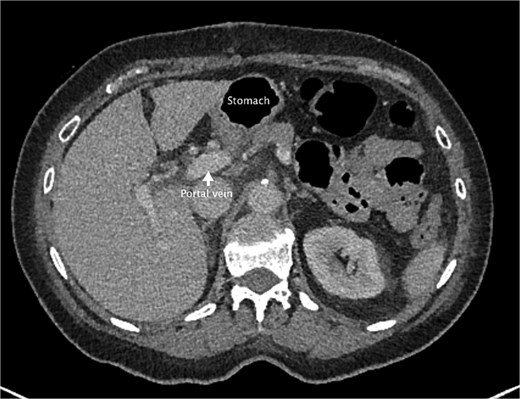

Postoperatively, she was commenced on a free fluid diet. She had a repeat CT abdomen and pelvis with portal venous phase contrast on day 1 postoperatively to reassess portal system blood flow. It showed reduced periportal oedema and normal filling of the portal vein and splenic vein. Previous findings were favored to be vascular venous congestion from the internal hernia rather than thrombus formation. The repeat CT also demonstrated diffuse splenic hypoattenuation likely related to previous venous outflow obstruction and will likely resolve. Clinically, she progressed well postoperatively. She began passing flatus on day 2 postoperatively, bowels were open on day 5 after commencing a gentle osmotic laxative on day 4 after her operation. She was discharged home on day 5. She was followed up in the surgical outpatient clinic 4 weeks after her discharge. At this follow-up, she had been well since the operation, and no further intervention was required (Fig. 6).

An axial slice from the post-operative CT abdomen pelvis in portal venous phase. There is an arrow pointing to the portal vein that has returned to normal size. Also labeled is the stomach now lying anteriorly rather than the colon.